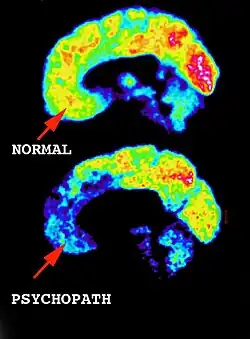

The idea of biological markers creating the underlying motivation for serial killers is being widely researched and has shown abnormal aspects within serial killers compared to healthy individuals (Zak, 2013). Ideas such as the ‘evil gene’ have been thoroughly researched but no conclusive evidence has been shown (Rose, 2000). Abnormal brain functioning, including lower brain capacity and defects within the hormonal levels have empirical evidence suggesting they can contribute towards someone becoming a serial killer (Winerman, 2004).

Other biological reasoning has been suggested by researchers. Winerman (2004) revealed that high testosterone levels combined with low serotonin levels can lead to aggressive and sadistic behaviour. This means the individual is more susceptible to other motivators that can lead to becoming a serial killer. Winerman also showed evidence that high levels of toxic metals such as magnesium, lead, cadmium and copper have been found in higher traces in past serial killers. These metals cause serotonin and dopamine levels to lower, contributing to aggressive behaviour.

Brain Defects

Another form of biological trauma is brain defeats, like lower IQ or head damage at a young age. Michaurd’s and Aynesworth’s research in 1999 showed that 29% of serial killers were found to be accident prone. The idea that brain defects lead to a predisposition to serial killing has been suggested in this study but there is no imperial evidence as of yet, more research should be done into the concept before this concept is sound. Debra Brown, as mentioned earlier was one part of a Serial killer couple. She showed no remorse to the 8 killings she was a part of but due to her low IQ, which had been apparent since a young age, combined with her non-violent history before meeting Cole she was given a lesser charge. It is thought that she was very susceptible to Coleman’s control and therefore she wasn’t explicitly responsible for what she was a part of. Through Michaurd and Aynesworth’s research in 1999 it was concluded that there are links between aggression and impaired executive brain functioning, like lower IQ. Therefore, serial killers such as Brown may just be reacting with neurological damage and basic instinct, combined with the strong control of someone dominant within their life, rather than on pure evil.